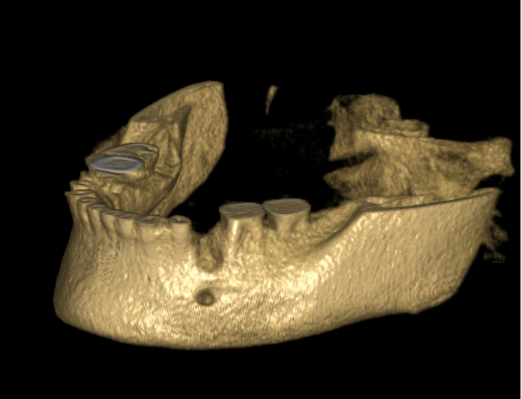

Tyto postupy nám umožní doplnit chybějící množství kosti v čelistech pacienta i zlepšit kvalitu kosti. Většinou se setkáváme s omezenou nabídkou kostní tkáně díky resorpčním (úbytkovým) procesům způsobených věkem či vytržením zubu, přítomností anatomických struktur jako je čelistní dutina, nervový kanál nebo patologických či poúrazových stavů - cysty, zlomeniny.

V těchto případech musíme použít některou z následujících pomocných metod:

Jedná se o augmentační metodu při dostavbách kosti a defektech kosti horní a dolní čelisti.

Při ztrátě molárů a premolárů v horní čelisti a jejich náhradě implantáty se často setkáváme s nedostatečnou vertikální nabídkou kosti pod čelistní dutinou, často doprovázenou i nedostatečnou horizontální nabídkou a sníženou kvalitou kosti

(v oblasti 2. premoláru v 50%, v oblasti moláru až v 80% případů nedostatečná kostní nabídka)